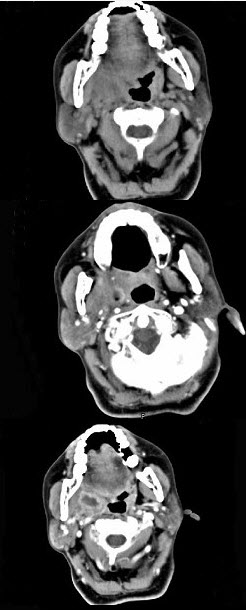

一男性患者,持续左耳流脓10年,检查示左侧35dB下降的传导性耳聋,如图分别为他的鼓膜外观和颞骨CT检查,可诊断为()。

A:慢性化脓性中耳炎单纯型

B:慢性化脓性中耳炎骨疡型

C:慢性化脓性中耳炎胆脂瘤型

D:急性中耳炎

E:以上都不是